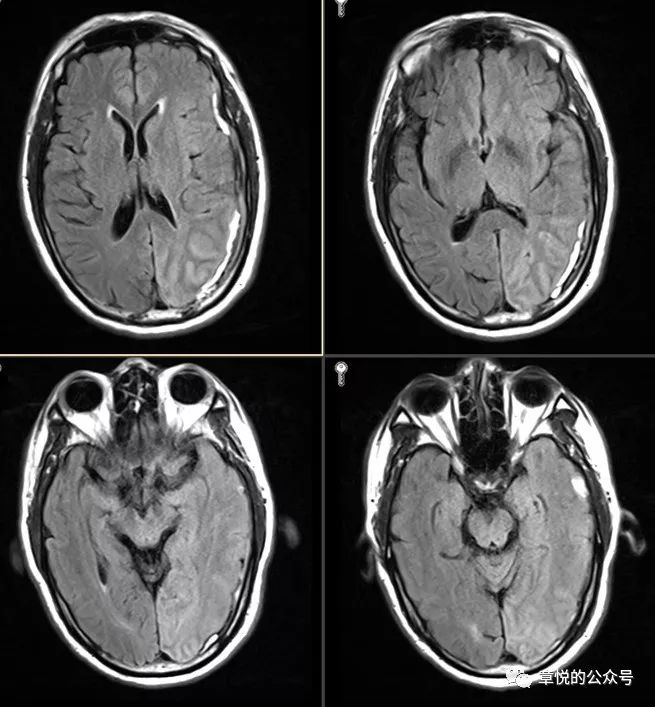

入院后予丙戊酸钠、左乙拉西坦和妥泰抗癫痫治疗,但住院3天患者依旧每天都有癫痫发作,表现为双眼向右侧视,头向右侧转,意识丧失,每次数分钟,发作间期意识模糊,萎靡不振,最多只能说出两三个字,行头颅MRI见左侧硬膜下血肿,并可见左侧颞枕叶肿胀,T2,FLAIR及DWI为略高信号。(图2)腰穿压力生化常规正常。

图2.FLAIR相左侧颞枕叶肿胀,信号增高